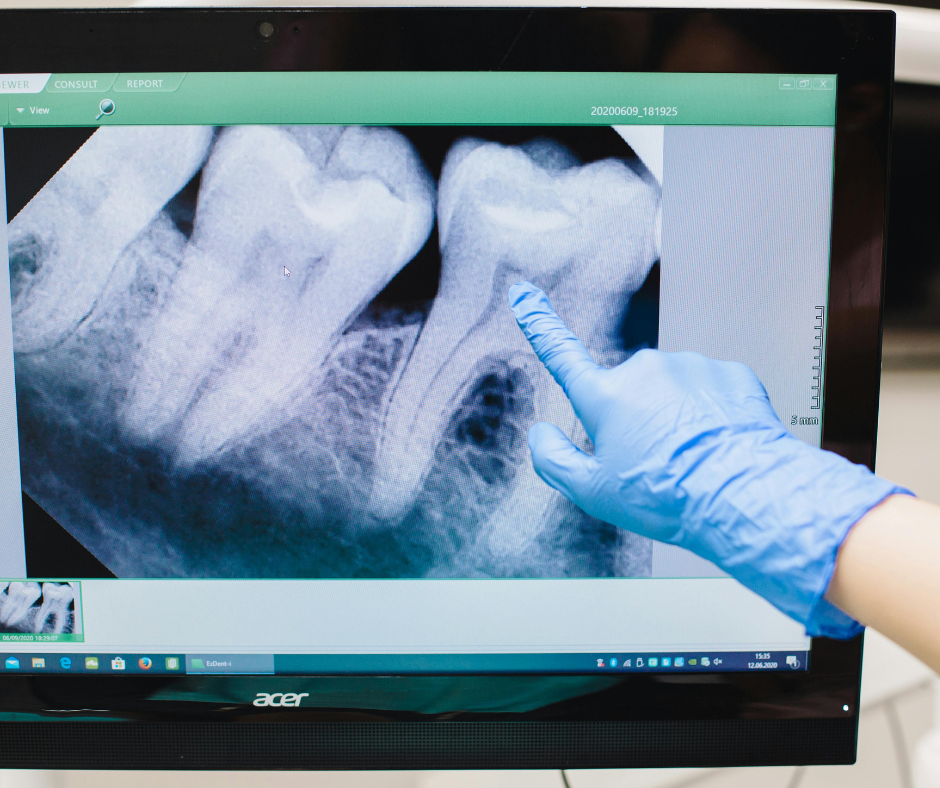

- Clinical Examination & Digital Imaging To assess tooth position, root structure, and proximity to nerves.